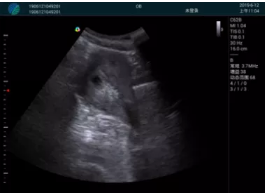

甲狀腺囊性結節(jié),囊壁鈣化,透聲好

甲狀腺囊性占位

M20查看:囊內回聲均勻,邊界清晰,囊壁光滑

M20引導抽吸術后囊腫消失,原區(qū)域空腔形成,脂肪層與腺體層架構發(fā)生改變